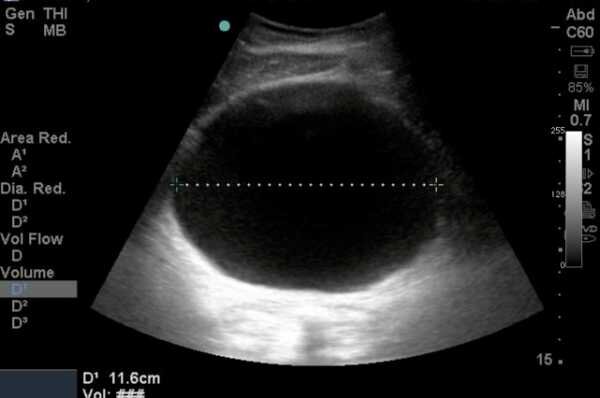

1 Больше всех поглощают ультразвук ( самые черные на изображении)

Это полости заполненные жидкостью ( сосуды, кисты, наполненный мочевой пузырь), они будут выглядеть на снимках как полностью или практически полностью черные структуры